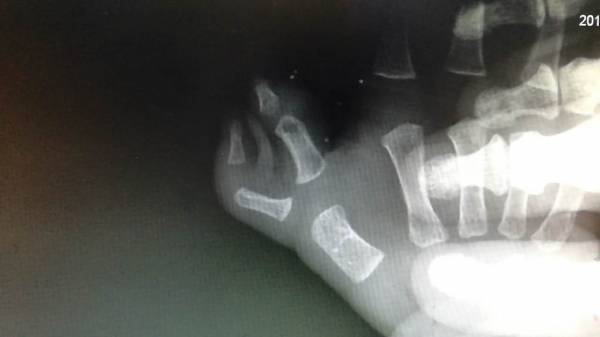

明天准备手术小孩

双手复拇畸形

微信图片_20170427164904.jpg

微信图片_20170427164908.jpg